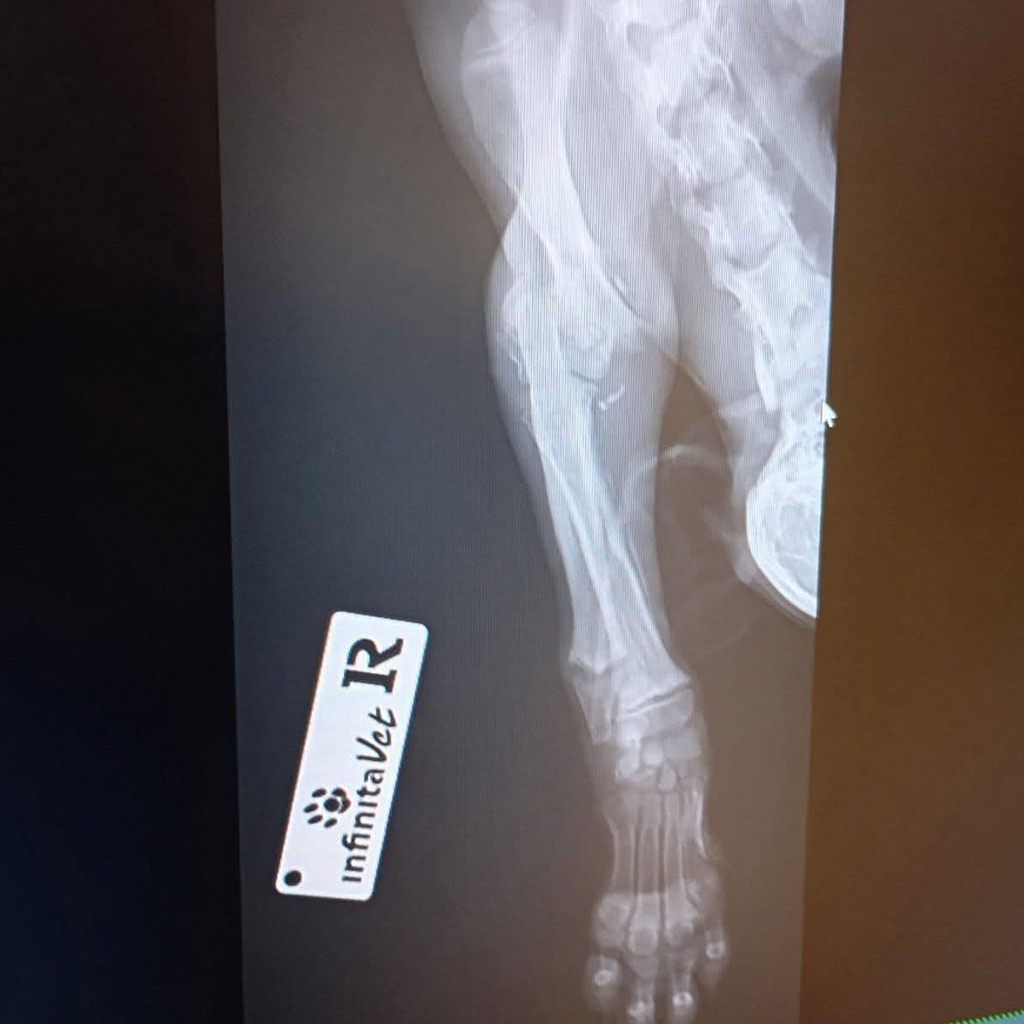

Zum Glück wurde Luca gefunden und sofort in eine Tierklinik gebracht. Dort folgte die erschütternde Diagnose: Ein Vorderbein und ein Hinterbein sind gebrochen. Die Röntgenbilder bestätigten das ganze Ausmaß ihrer Verletzungen.

Die Fraktur am Hinterbein kann ohne Operation ausheilen, hier ist strenge Schonung ausreichend.

Doch das Vorderbein ist so schwer verletzt, dass eine Operation dringend notwendig ist. Um eine stabile und dauerhafte Heilung zu ermöglichen, muss ein Metallimplantat eingesetzt werden. Nur so hat Luca die Chance, später wieder schmerzfrei zu laufen und ein normales Hundeleben zu führen.